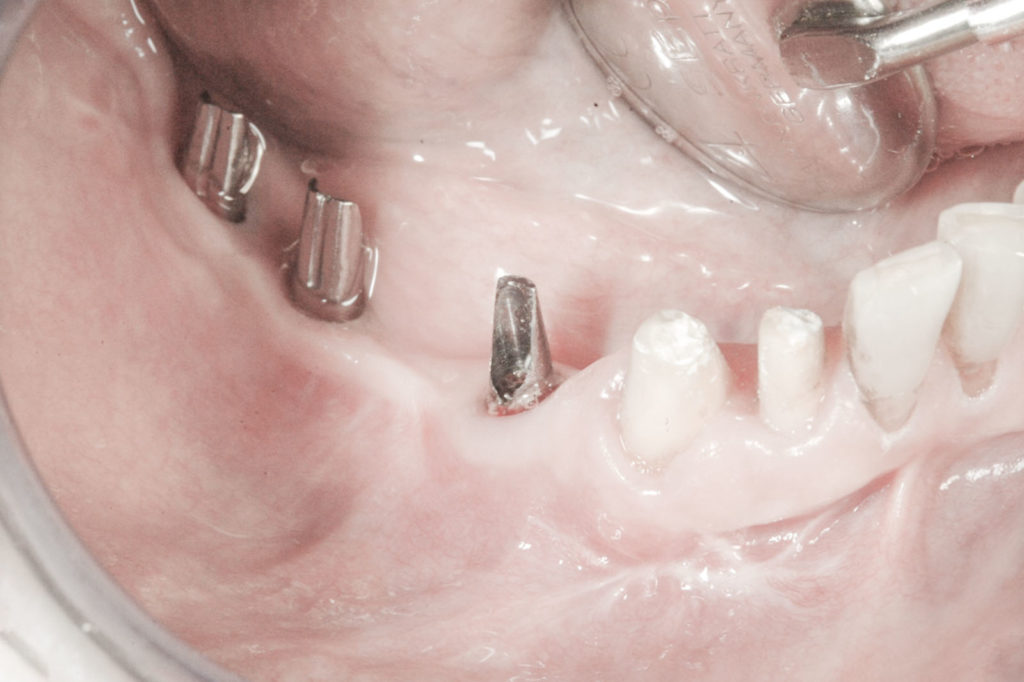

Procedury te są stosowane w sytuacji niedostatecznej ilości kości, skutkującej odsłonięciem gwintu, podczas gdy wszczepiamy implanty stomatologiczne lub też jako zabiegi poprzedzające ich wprowadzenie.​

• Użycie drobin kości własnej do pokrycia ubytków na niewielkim obszarze, jak obnażenia gwintu implantu podczas implantacji, obnażenie korzeni zęba czy furkacji korzeniowych. Wiórki kostne pobierane są podczas zabiegu specjalnymi aplikatorami (skrobaczkami) z powierzchni kości szczęk i żuchwy.